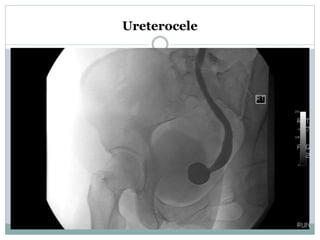

IVU:

 Ureterocele- a "cobra head" or "spring onion"

configuration at bladder level.

Ureterocele